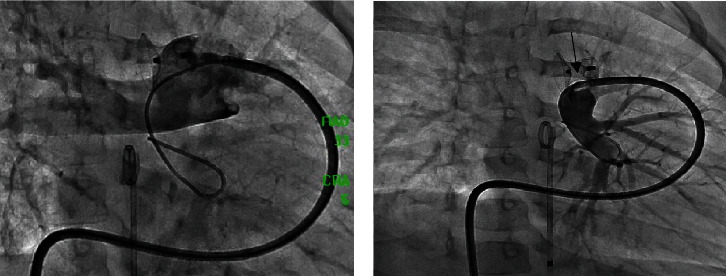

Percutaneous device occlusion is currently the standard of care for most cases of patent ductus arteriosus (PDA). Albeit infrequent, device-related left pulmonary artery (LPA) stenosis is a known complication of this procedure, occasionally requiring stent placement to relieve the obstruction. We present a series of four patients who required left pulmonary stenting after ductus arteriosus device closure. A review of the current evidence is presented.

Abstract Image